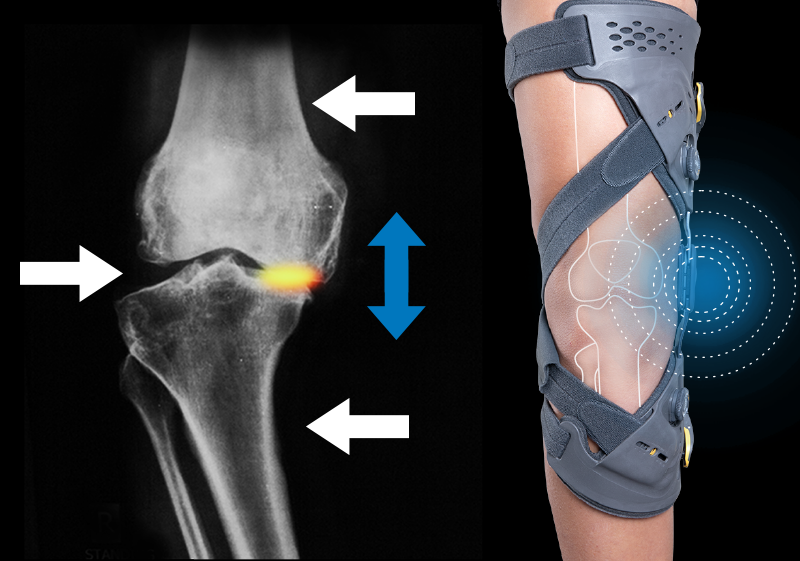

°ñ°üÀý¿°(OA)ÀÇ ´Ü°è´Â ¿¢½º·¹ÀÌ ÃÔ¿µÀ» ÅëÇØ È®ÀÎÇÒ ¼ö ÀÖÀ¸¸ç ͱ׷£ ·Î·£½º µî±Þ »ó KL 0 - KL 4 ´Ü°è·Î ºÐ·ùµË´Ï´Ù.

¹«¸ ¿¬°ñ Ç¥¸éÀÌ ´â±â ½ÃÀÛÇÏ´Â ´Ü°è·Î ¿¢½º·¹ÀÌ ¶Ç´Â MRI »ó ¸Å¿ì ÀÛÀº µ¹ÃâºÎ, ±Õ¿, ÇÔ¸ô µîÀ» È®ÀÎÇÒ ¼ö ÀÖ½À´Ï´Ù. ÀÌ ´Ü°èÀÇ È¯Àڴ ƯÈ÷ ¿À·£ °È±â ÈÄ¿¡ ÅëÁõÀ̳ª ºÒÆíÇÔÀ» ´À³¥ ¼ö ÀÖ½À´Ï´Ù. Ãʱ⿡´Â ÆûÇÍÇÁ·Î ´Ï OA¿Í °°Àº °¡º¿î Á¦Ç°À» Âø¿ëÇÏ¿© ¹«¸ ÅëÁõÀ» ¿ÏȽÃŰ°Å³ª ¿¬°ñ ¼Õ»óÀÌ ÁøÇàµÇ´Â °ÍÀ» ¹æÁöÇÒ ¼ö ÀÖ½À´Ï´Ù.

°ñ°üÀý¿° Áß±â´Â ¿¬°ñÀÌ ´â±â ½ÃÀÛÇØ¼ »À³¢¸® ÀÚÁÖ ºÎµúÈ÷°Ô µË´Ï´Ù. ÀÌ ´Ü°èÀÇ È¯ÀÚ´Â °È±â, ¶Ù±â, ±ÁÈ÷±â, °è´Ü ¿À¸£±â µîÀÇ È°µ¿ ½Ã ÅëÁõÀ» ´À³§´Ï´Ù. ¿À·¡ ¾É¾ÆÀְųª ¿À·¡ ´©¿öÀÖÀ¸¸é ¹«¸ÀÌ »»»»ÇØÁö´Â°Íµµ ÈçÇÏ°Ô ³ªÅ¸³ª´Â Áõ»óÀÔ´Ï´Ù. À¯¿¬¼ºÀÌ °¨¼ÒµÇ¸ç ÀÏ»ó Ȱµ¿ ¹× Ãæ°ÝÀ¸·Î ÀÎÇØ Áõ»óÀÌ ¾ÇȵDZ⠽±½À´Ï´Ù. À±È°¾×ü(Ȱ¾×) ¶ÇÇÑ ÆÄ±«µÇ±â ½ÃÀÛÇØ¼ Á¦ ±â´ÉÀ» ÇÏÁö ¸øÇÏ°Ô µÇ¾î ¿¬°ñ¿¡ ±Õ¿ ¹× ±¸¸ÛÀÌ °è¼Ó ³ªÅ¸³³´Ï´Ù. ¹«¸¿¡ ¹«¸®°¡ °¡´Â Ȱµ¿À» ÇÏ°Ô µÇ¸é ¹«¸ ¿°ÁõÀÌ ¹ß»ýÇϱ⵵ ÇÕ´Ï´Ù. Áß±âÀÇ °æ¿ì º¸´Ù °ÇÑ ÈùÁö¿Í ½ºÆ®·¦ÀÇ ÆûÇÍOA·¦¾î¶ó¿îµå Âø¿ëÀ» ÅëÇØ ÅëÁõÀ» ÁÙÀÌ°í ¿¬°ñ ¼Õ»óÀ» ¹æÁöÇÒ ¼ö ÀÖ½À´Ï´Ù.

ÀÏ»ó»ýȰ Áß ½É°¢ÇÑ ÅëÁõ°ú ºÒÆíÇÔÀ» ´À³¢°Ô µË´Ï´Ù. ÀÌ ´Ü°èÀÇ ¿¬°ñÀº ¿ÏÀüÈ÷ ´â¾Æ »À »çÀÌ °ø°£ÀÌ ½É°¢ÇÏ°Ô ÁÙ¾îµé¾î ¿¬°ñÀÌ »À¸¦ º¸È£ÇÏÁö ¸øÇÏ´Â »óŰ¡ µË´Ï´Ù. °üÀý À±È°À¯ÀÇ ¿ªÇÒÀ» ÇÏ´Â °üÀý³¶¾×µµ ÁÙ¾îµé¾î ¿òÁ÷ÀÏ ¶§ ¸¶ÂûÀ» ÁÙ¿©ÁÖÁö ¸øÇÏ°Ô µË´Ï´Ù. ¿òÁ÷ÀÏ ¶§ »À°¡ ¼·Î »ß°Æ°Å¸®°Å³ª ºÐ¸®µÈ ÀÛÀº ¿¬°ñ Á¶°¢µéÀÌ °üÀý ÁÖÀ§¿¡ ¶°´Ù´Ï¸é¼ ½ÉÇÑ ÅëÁõ°ú ¼Õ»óÀÌ À¯¹ßµË´Ï´Ù. ¿ÜºÎÀûÀ¸·Î´Â ´Ù¸®°¡ ½É°¢ÇÏ°Ô ±Á¾îÁö´Â °ÍÀ» À°¾ÈÀ¸·Î È®ÀÎÇÒ ¼ö ÀÖ½À´Ï´Ù. ¸»±âÀÇ °æ¿ì ÅëÁõ °æ°¨ È¿°ú°¡ ÀÓ»óÀûÀ¸·Î Áõ¸íµÈ ¾ð·Î´õ¿ø Âø¿ëÀ» ±ÇÀåµå¸³´Ï´Ù.

¹«¸ °ñ°üÀý¿°À¸·Î ÀÎÇÑ ÅëÁõÀÓÀÌ È®ÀÎµÈ °æ¿ì ¿À¼ÀÇ °ñ°üÀý¿° º¸È£´ë¸¦ Âø¿ëÇØ ÅëÁõÀ» °æ°¨½Ãų ¼ö ÀÖ½À´Ï´Ù.